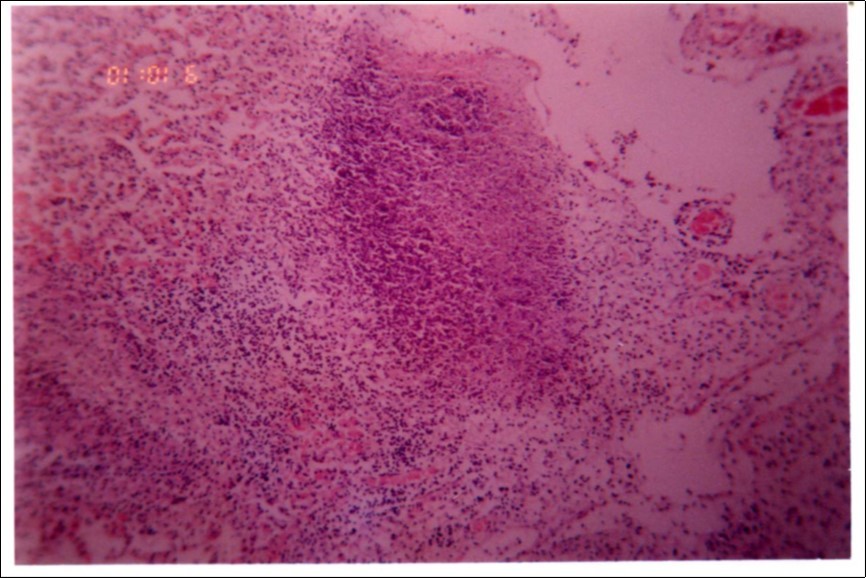

Figure 3, Figure 4 and Figure 5 show different histopathological pictures of hepatized lung tissue samples from which Mmm isolates were recovered. In Figure 3, widened interlobular septa, due to presence of fibrinous necrosis and cellular infiltration were observed. Figure 4 shows extensive loss of airspace due to necrosis and infiltration of neutrophils. Figure 5 shows hyperemia of alveolar wall capillaries and infiltration of few fibrin and neutrophils.

Figure 4.Extensive loss of air space due to necrosis and infiltration of neutrophils (H&E ×100).

Although no advanced techniques like PCR were used to identify the isolates, procedures used in this study were quite enough to confirm the incidence. Affected animals with CBPP were diagnosed based on the clinical signs, the PM findings, the typical histopathological picture in addition to the isolation of the causative agent and its subsequent identification using cultural and biochemical procedures. Identification of the isolates was confirmed by the growth inhibition test as recommended in OIE manual 10. The histopathological sections of diseased lungs, from which Mmm (SC) was isolated, showed typical histopathological picture of CBPP. The CBPP lesion comprises abronchiolar necrosis and oedema which progress rapidly to an exudative serofibrinous bronchiolitis with extension to the alveoli and uptake of alveolar fluid into tissue spaces 17, lymphatic vessels and ultimately septal lymphatics 18. With stasis, lymphatic vessels become thrombosed and ultimately fibrosed 19. The histological section of the lung in acute stage of the disease showed odema in the lymphatics of the interlobular septa and interstitial tissue and massive infiltration of fibrin, macrophage and neutrophils into the alveolar lumen 20. Also there was presence of lymphocytes and alveolar macrophages around the lymphatic vessels and septa margin 21. These findings supported the isolation results and gave additional evidence for the diagnosis of the disease.